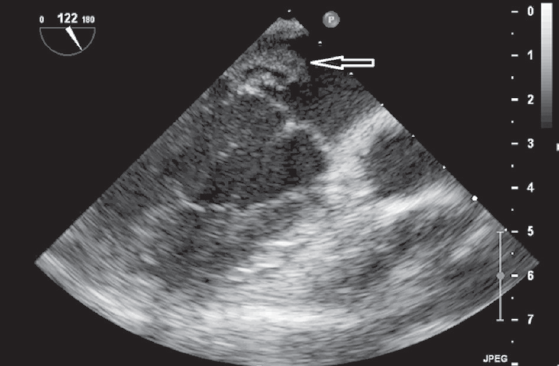

The optimal time for surgery on the heart valves in patients with active infectious endocarditis (IE) is still controversial. It is a well known fact that cerebral, coronary or renal thromboembolism is the most common cause of death in patients with left-sided IE. Thromboembolism can develop before the appearance of clinical manifestations of the destruction of the valvular apparatus of the heart. Currently, early surgical intervention is considered as the most effective method of treatment of many forms of active left-sided IE. Early surgery involves performing surgical correction until the completion of a full antibiotics course. We present the clinical case of early surgical correction of the patient (A., 16 years) with mitral valve infectious endocarditis. The disease was acute, with recurrent embolisms to the right kidney with infarction and to the left clavicle with osteomyelitis. Surgical intervention was performed as a matter of urgency; surgical access – right-sided anterolateral thoracotomy. The girl was operated on the 4th day of the hospitalization to our hospital. However, time of treatment was lost at the prehospital stage and rapid mitral valve destruction did not allow to repair the valve. Therefore, the mitral valve replacement was performed. The postoperative period was favorable. On the 3rd day after the operation, the girl was transferred to the cardiology department. On control ECHO after 3 years: myocardial contractile function is good, EF 65%, the function of the MV prosthesis is not impaired.